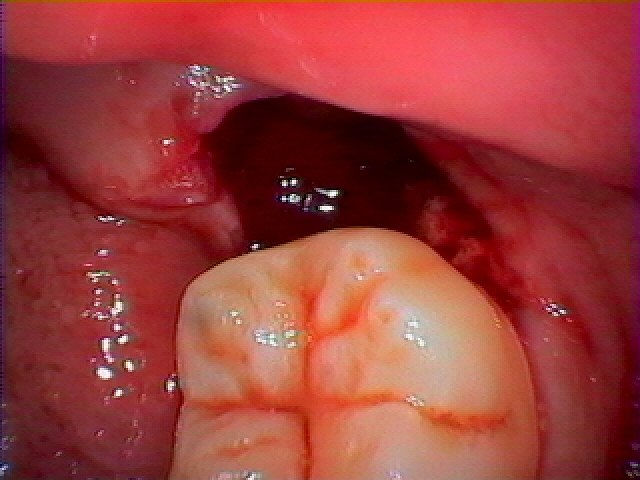

親知らずになります

完全に横を向いてしまい、物が詰まっています

親知らずにも大穴

これが最近の痛みが強くなってきた原因かと思います

歯茎の炎症もあり幾分出血しやすくなっています